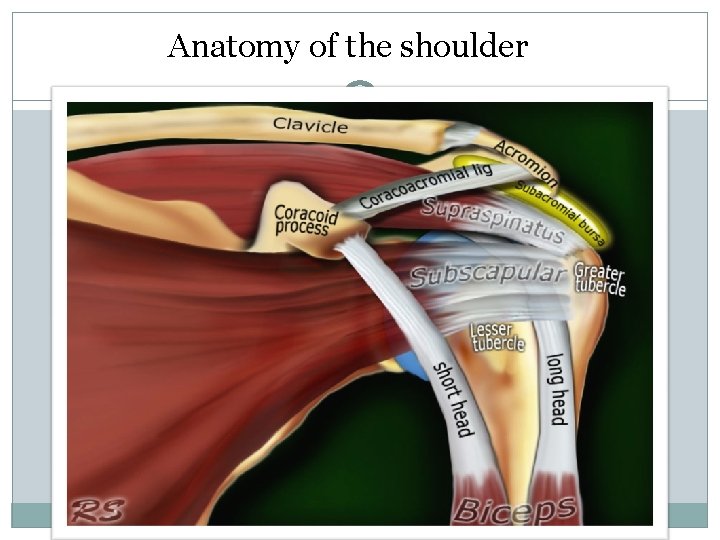

Anatomy of the shoulder

Anatomy of the shoulder

shoulder joint is the most mobile joint of the body Joints The shoulder consists of three joints: 1 -Acromioclavicular 2 -Sternoclavicular 3 -Glenohumeral joint And two gliding planes: 1 -Scapulothoracic 2 -Suacromial

Anatomy of the shoulder

Anatomy of the shoulder